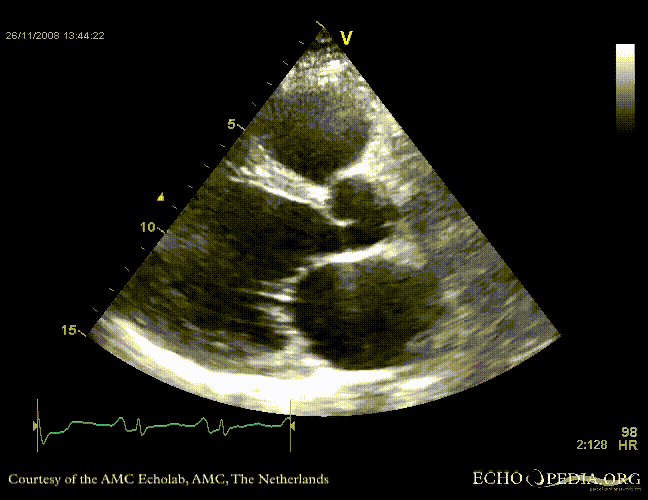

Dilated cardiomyopathy with severe mitral valve regurgitation

Courtesy of: J. Vleugels, AMC, The Netherlands